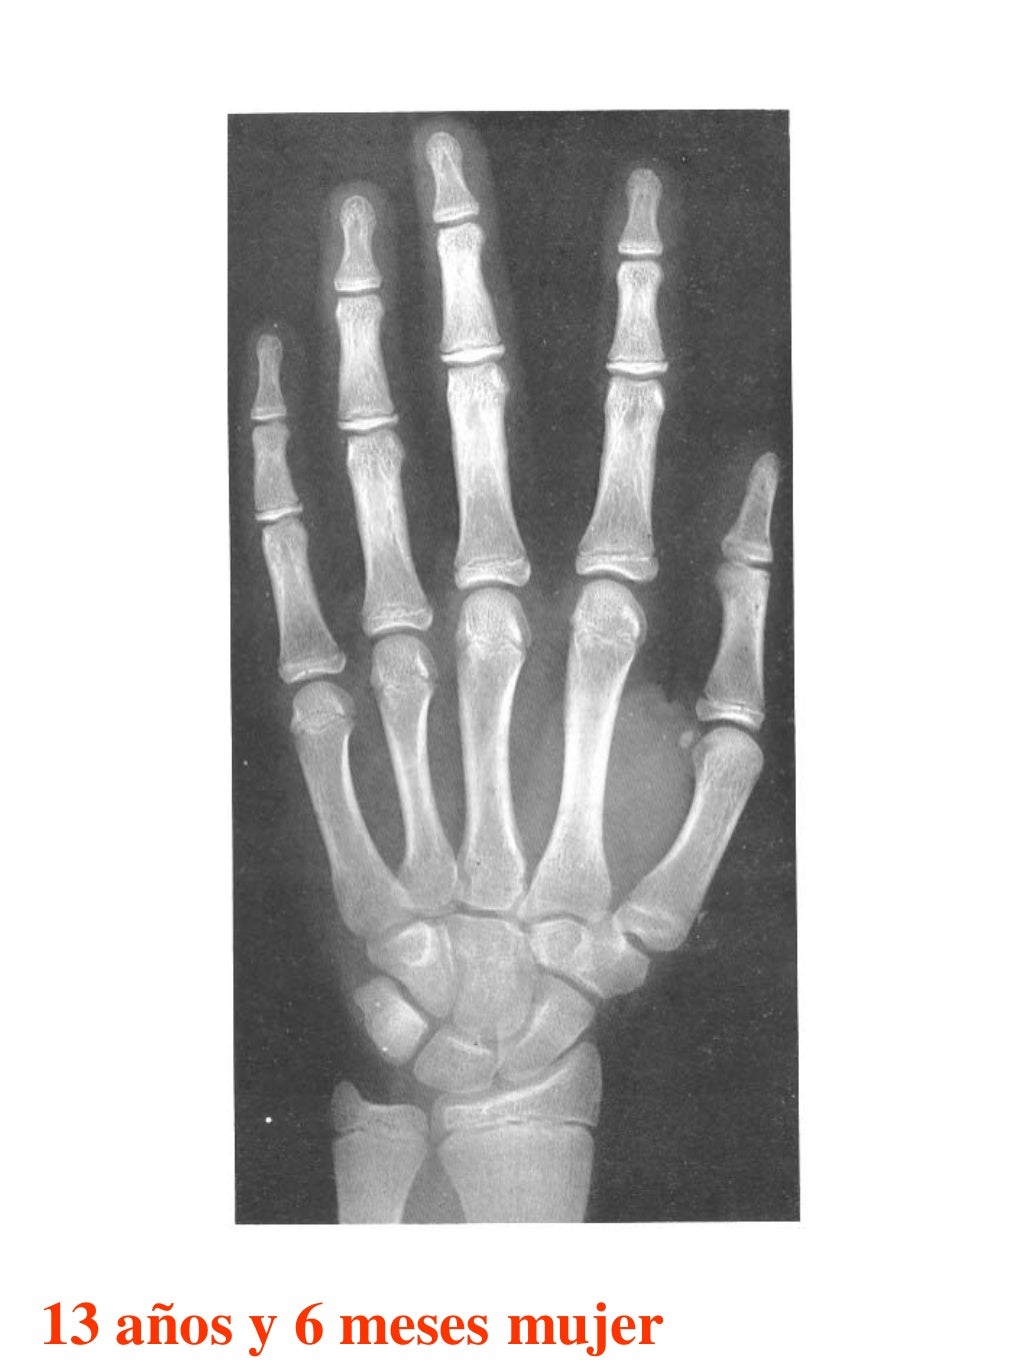

Figura 2 Imágenes de radiografías de mano y muñeca izquierda del

Figura 2 Imágenes de radiografías de mano y muñeca izquierda del Tablas De Greulich Y Pyle Edad Osea The greulich and pyle atlas is used to estimate the age of children and adolescents. El método de greulich y pyle(1) es un método simple de valoración de la edad ósea en pacientes pediátricos. El diagnóstico y la clasificación se basan en el examen físico, el análisis del crecimiento, la maduración ósea, la ecografía de útero y gónadas, y los. Tablas De Greulich Y Pyle Edad Osea.